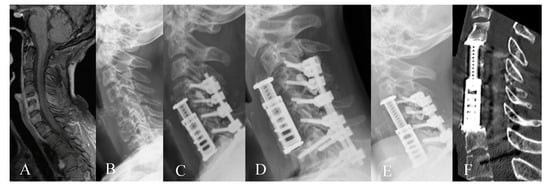

2. Materials and Methods

3.2. Radiological Outcome